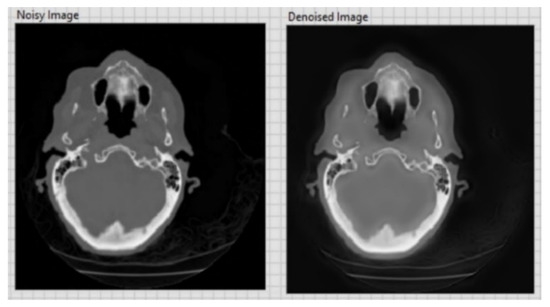

| CT image (Figure 6) 256 × 256 | 26.01 | 0.05 |

| CT image (Figure 7) 256 × 256 | 20.15 | 0.1 |

| CT image (Figure 8) 256 × 256 | 20.13 | 0.1 |

| CT image (Figure 9) 256 × 256 | 26.09 | 0.05 |

| CT image (Figure 10) 256 × 256 | 20.18 | 0.1 |

| CT image (Figure 11) 256 × 256 | 26.15 | 0.05 |